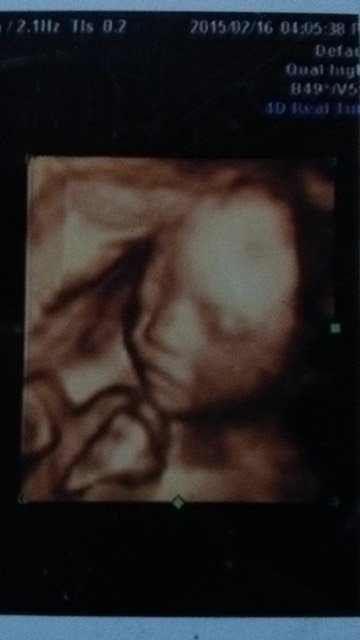

宝宝24周的四维照片,亲们猜猜男女 点击展开 可可👸妈咪 2015-03-04 17:59 为您推荐: 其他回答 刚刚六个月的宝宝,很难跟据面容来确定男女,需要B超下检查生殖器才能诊断。但是性别鉴定是非法的, nicexiaoru 2015-03-04 18:21 相关问题 四维照片到了,能猜出男女吗? 24周做四维彩超照片看着宝宝嘴大怎么回事 为什么做的四维彩超!B超单子宝宝照片是黑白的啊